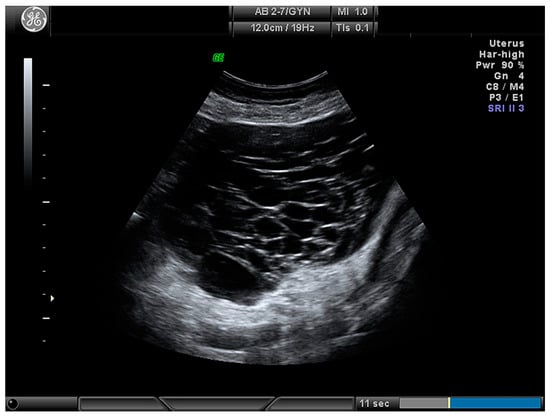

| Cystic–solid (Figure 4) | 61 (71.8) |